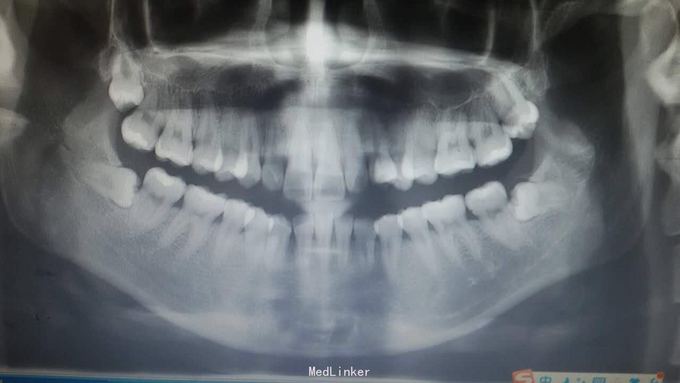

患者女,22岁,因智齿长期发炎就诊